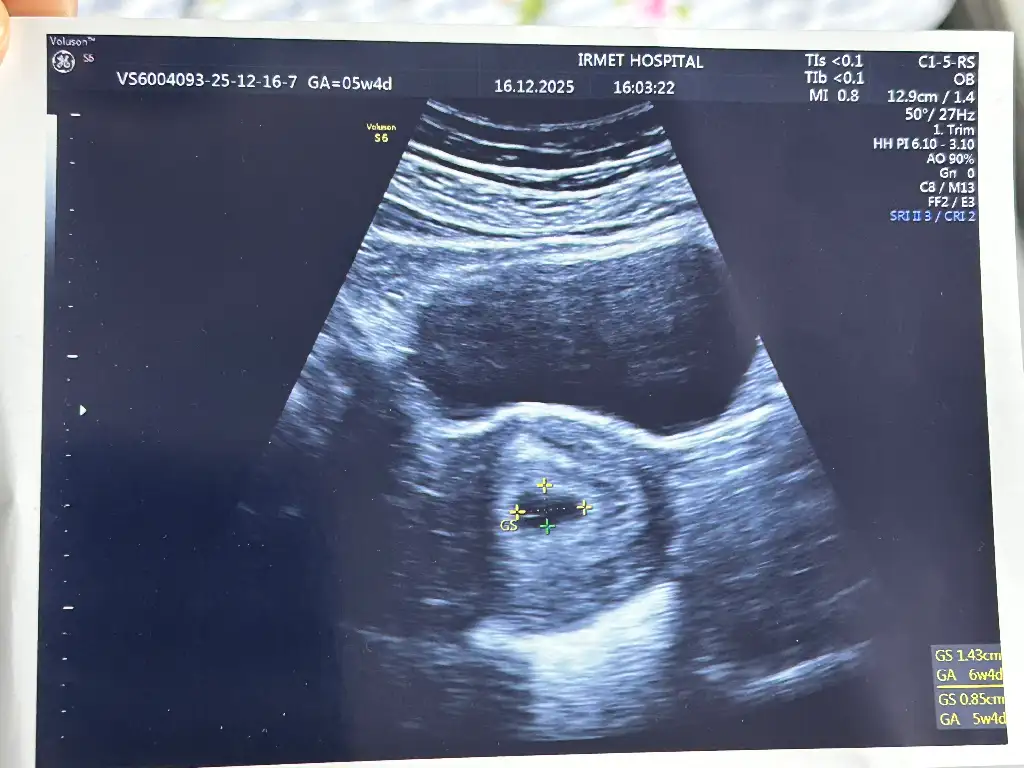

Kız o siyah boşluk ne oluyor üstteki büyükBen pike göre söyledim. Doktorun verdiği fotoda da öyle yazıyor. Son adet tarihi tahmini ne dedi. Ben de 30 ekim değil, 7 kasım söyledim. Uğraşmadım ona döngü anlatmaklafotoğrafı ekliyorum anlıyorsan sen de bak.

Chatgpt idrar torbası diyor. İdrara sıkışıktım bu aradaKız o siyah boşluk ne oluyor üstteki büyük

Ahaahahah mantıklıııChatgpt idrar torbası diyor. İdrara sıkışıktım bu arada![]()